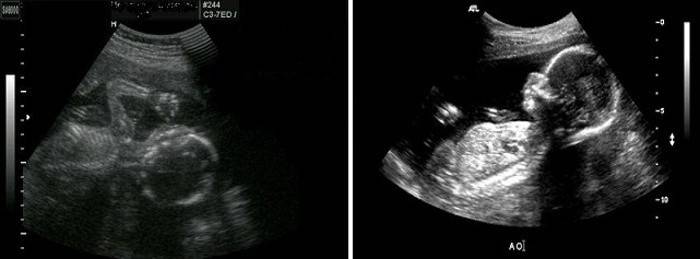

Ultrassonografia

Durante esse período, a maioria das mulheres é submetida à ultrassonografia como parte de uma segunda triagem de gravidez. Neste período, você especificará o sexo do seu bebê. Se possível, você pode ir e ultra-sonografia 3D do feto, onde você pode ver seu bebê em toda a sua glória. Mas para os especialistas em ultrassonografia é necessário não apenas determinar o sexo, mas também determinar os indicadores como:

- idade gestacional

- altura e peso fetal estimados,

- a localização da placenta e sua condição,

- quantidade e condição do líquido amniótico,

- o tamanho dos ossos do feto da circunferência do abdômen e da cabeça.

O médico avaliará a estrutura dos órgãos internos, avaliará os batimentos cardíacos fetais e a circulação sanguínea, além de verificar se o feto apresenta malformações congênitas e suspeitas de patologias genéticas. Se houver um nascimento anterior por CS, o médico irá avaliar a condição da sutura e fixação da placenta.